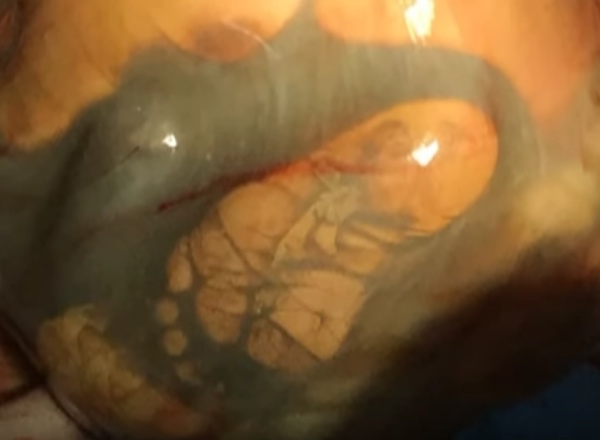

Bebek, kadının rahminde değil karın boşluğundaydı. Doktorlar, kadının dış gebeliği olduğunu anladılar. Dış gebelik, gebelik ürünü olan döllenmiş yumurtanın rahim boşluğu dışında yerleşmesiyle oluşan bir gebelik komplikasyonu.

Dış gebelik sonucunda dünyaya gelen bebeklerin çoğu maalesef yaşamıyor.Doktorlar, gerçeği öğrenir öğrenmez anne adayını hemen ameliyata hazırladılar. Bebeği dünyaya getirmek son derece zordu. Oluşacak birçok komplikasyon sonrası çocuğun dünyaya sağlıklı bir şekilde gelme şansı çok düşüktü.

Dış gebelik oluşan anne adaylarının bebeklerini dünyaya getirebilmeleri için sezaryen şarttır. Öte yandan plasentayı almak bile annede aşırı kanamaya neden olabilir.Operasyon tam iki saat sürdü.Doktorlar minik kızı dünyaya getirdiklerinde şok oldular. Küçük kız son derece sağlıklıydı ve 4 kilo ağırlığındaydı.